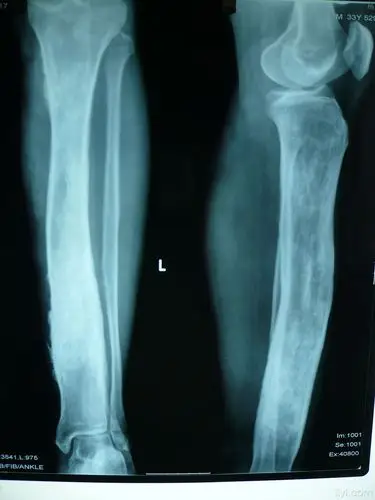

左胫骨慢性骨髓炎

胫骨骨髓炎 - 好大夫在线

这一例胫骨慢性骨髓炎大家有啥好建议